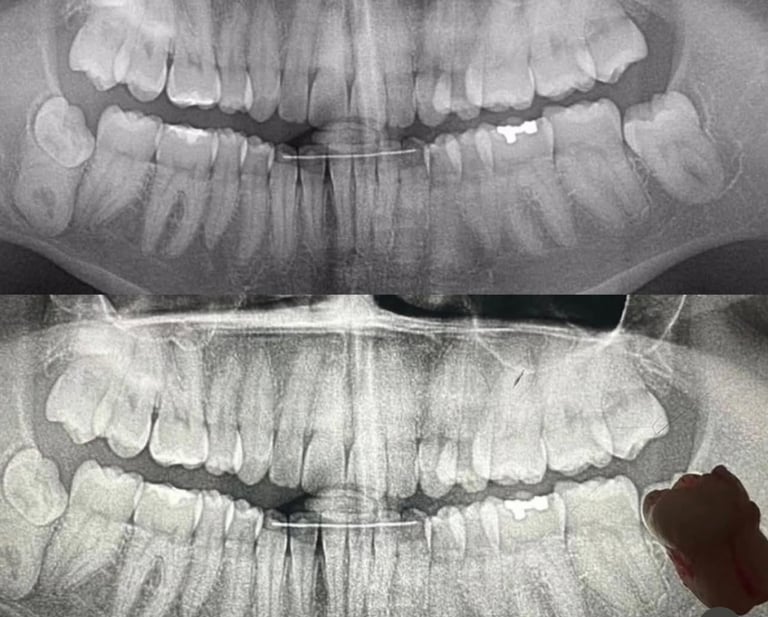

Endodoncia

La endodoncia es un procedimiento dental que consiste en eliminar la pulpa infectada o inflamada del interior del diente para salvarlo y evitar su extracción. Es una solución efectiva para aliviar el dolor, eliminar infecciones y restaurar la funcionalidad de la pieza dental. En nuestra clínica, realizamos tratamientos de endodoncia con tecnología de vanguardia y máxima comodidad, asegurando una recuperación rápida y resultados duraderos. Confía en nosotros para cuidar tu salud bucal y devolverle la vida a tu sonrisa.